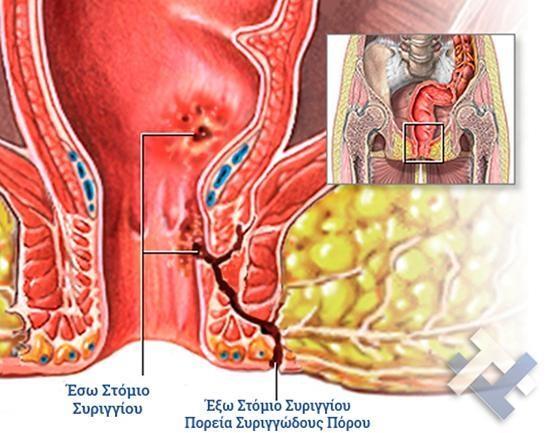

Ο Γενικός Χειρουργός Λιάγκος Γεώργιος MD PhD εκτελεί τις επεμβάσεις Λαπαροσκοπικά, Ενδοσκοπικά, Ανοιχτά Ελάχιστα Επεμβατικά και με Laser. Η θεραπεία εξατομικεύεται σε κάθε ασθενή ανάλογα με τις ανάγκες του. Αναλαμβάνει περιπτώσεις όπως κήλες και κοιλιοκήλες (αντιμετώπιση βουβωνοκήλης, αντιμετώπιση ομφαλοκήλης, θεραπεία επιγαστρικής κήλης, κήλη των αθλητών (Σύνδρομο κοιλιακών προσαγωγών), αντιμετώπιση μετεγχειρητικής κήλης, θεραπεία Μηροκήλης), πέτρες στη χοληδόχο κύστη, λαπαροσκοπική χολοκυστεκτομή, αντιμετώπιση Κύστη Κόκκυγος με λέιζερ (laser), παθήσεις πρωκτού, χειρουργική laser σύγχρονων κυκλικών ινών (αιμορροΐδες αντιμετώπιση, θεραπεία αιμορροϊδων με laser (LHP), αφαίρεση αιμορροΐδων με υπερήχους (HALL-RAR), χωρίς Χειρουργείο με ελαστικούς δακτυλίους (Τεχνική BARON-RBL), θεραπεία ραγάδας πρωκτού (Ραγάδα δακτυλίου), θεραπεία περιεδρικού συριγγίου, θεραπεία περιεδρικού αποστήματος, κονδυλώματα πρωκτού Θεραπεία, δερματικό ράκος (Skin tag) εκτομή, αντιμετώπιση Kνησμού, καρκίνος πρωκτού θεραπεία), παθήσεις Δέρματος, χειρουργική με laser CO2, αφαίρεση μορφωμάτων δέρματος - βιοψίες, αφαίρεση ελιάς (Σπίλου), σμηγματογόνος κύστης θεραπεία, αφαίρεση λιπώματος, είσφρυση όνυχος χειρουργείο, καρκίνος δέρματος θεραπεία, οξεία σκωληκοειδίτιδα, παθήσεις Λεπτού και Παχέος Εντέρου, ειλεός λεπτού εντέρου, εκκολπωμάτωση (Εκκολπωματίτιδα) σιγμοειδούς, καρκίνος παχέος εντέου, κολοστομίες, port χημειοθεραπείας κ.α. εξυπηρετώντας Παγκράτι και γύρω περιοχές.